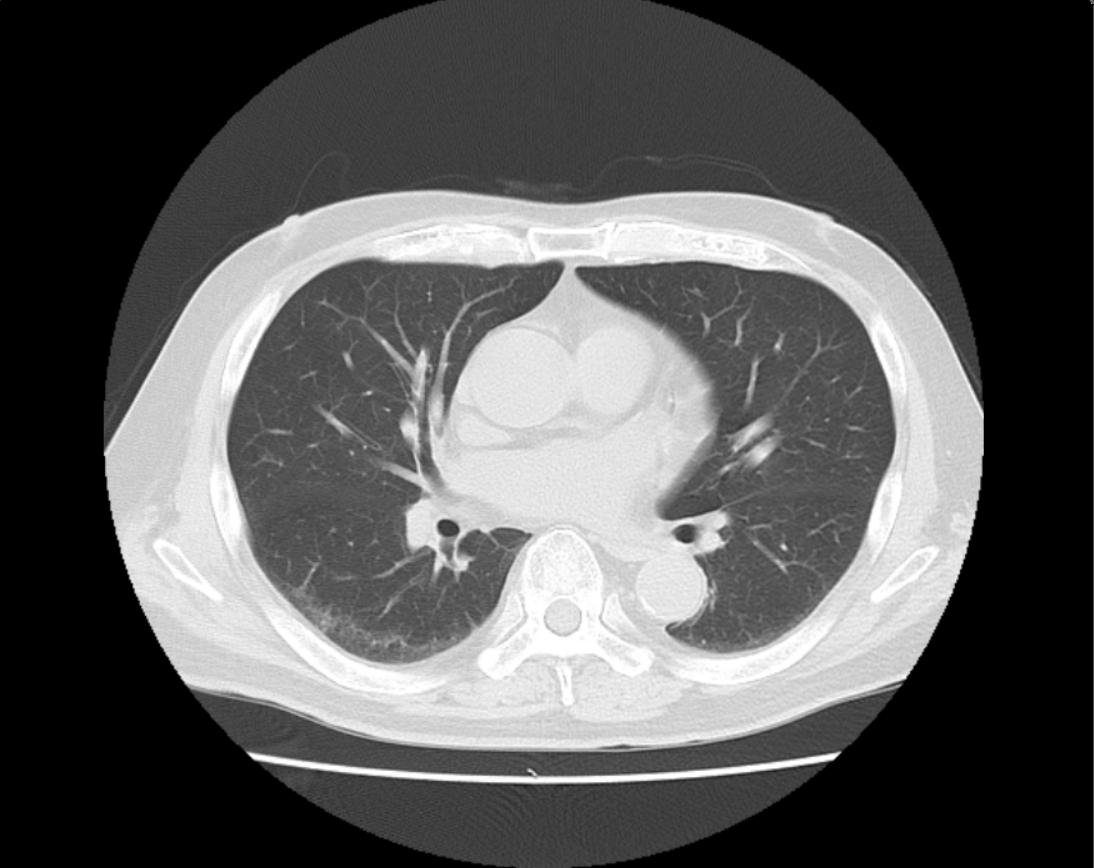

CT Aquilion lightningの導入

当院では新しいCTを導入いたしました。

高速マルチスライスでの撮影によって、従来のCT検査よりも短い時間で検査を受けることが出来ます。

撮影の際、体の部位に対して最適線量での撮影を自動調整できるため、被ばく低減が可能になりました。

新しいCTでは開口径を780㎜と広くすることによって狭い場所が苦手な方でも安心して検査を受けていただけます。